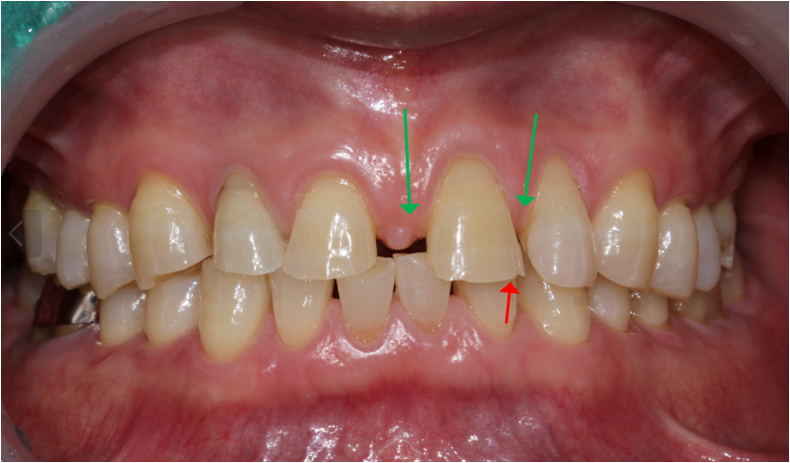

[ 초진 시 구강 상태 ]

- 앞니가 벌어지고 최근에 식사하다가 깨짐

- 어릴 때부터 앞니벌어짐이 콤플렉스였는데 최근에 깨져서 더 신경쓰이는 상태

- #12 치아는 어릴 때 신경치료를 받은 상태

- 전치부 교합이 강해 위, 아래 앞니 마모가 심한 상태

- 강한 교합으로 상악 앞니가 점점 벌어지고 있는 상태

- 마모가 심해 날카로워졌고 날카로워진 부위가 파절되어 내원